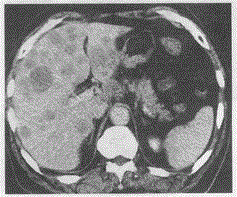

胃癌术后2年,上腹部疼痛,肝脏增强后如图最可能的诊断是A.肝转移B.肝脓肿C.肝囊肿D.肝癌E.肝包虫病

问题 胃癌术后2年,上腹部疼痛,肝脏增强后如图最可能的诊断是

选项 A.肝转移 B.肝脓肿 C.肝囊肿 D.肝癌 E.肝包虫病

答案 A